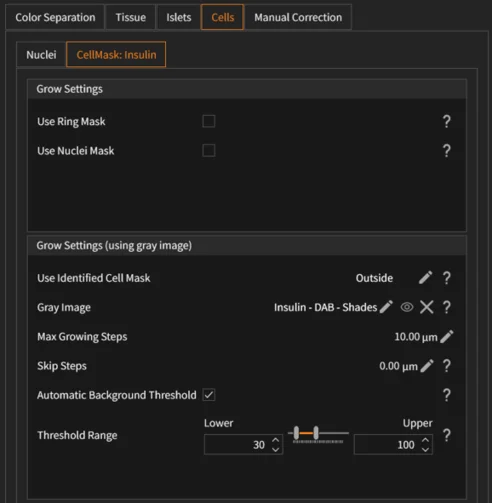

The IHC Immune Status in Situ App allows users to adjust tissue classification, cell detection, phenotype gating, and spatial analysis parameters:

- Cellular mask (immune marker channel): Generate cytoplasmic masks on the DAB channel; define automatic/manual background threshold, threshold range, max growing steps, and interior/exterior growth radius.

- Phenotype gating: Define cutoffs in area–intensity plots (Cellular Mask DAB mean intensity vs. area) to select positive immune cells.